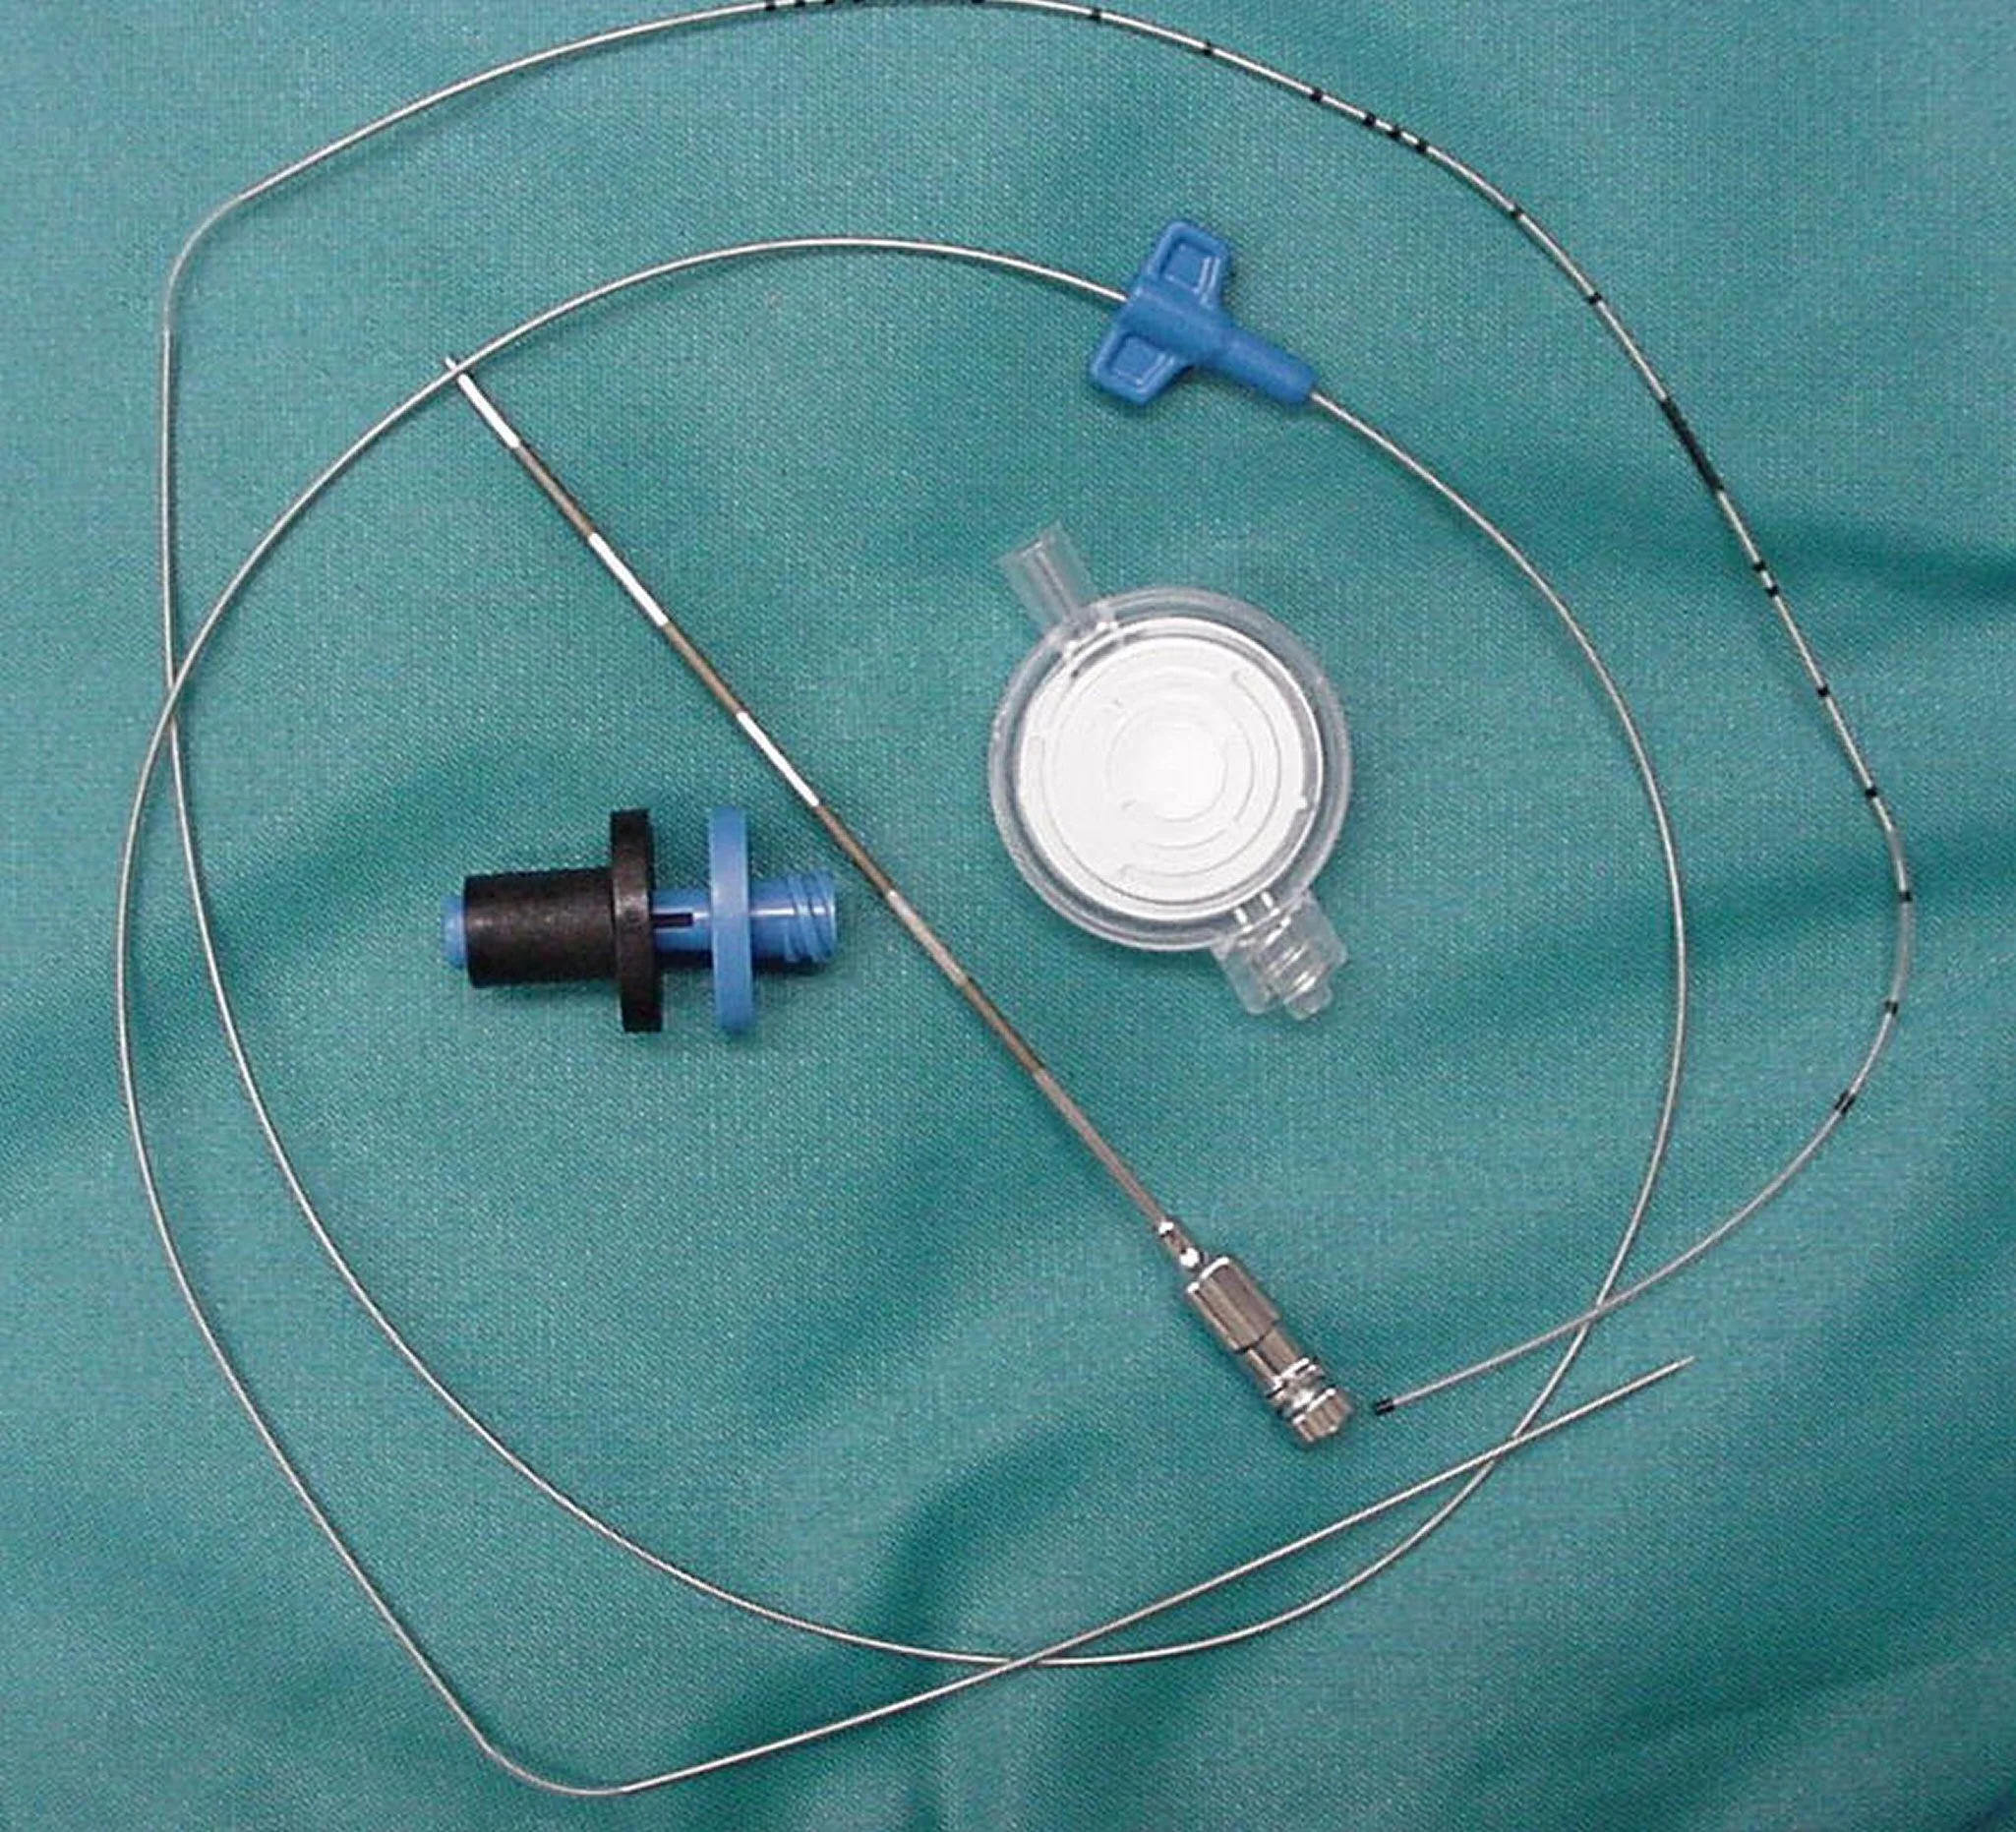

Complete epidural catheter kit (Figure B) or

Tuohy or Hustead needle with catheter (Figure C)

Very few complications have been associated with epidural catheters placed for periods ranging from 1 to 7 days in dogs.7 There are no large-scale reports of their use in cats. Many different commercially available epidural catheter kits designed for humans, children, and animals have been used clinically in dogs and cats. The procedure is similar to that described above. However, the needle that comes with the kits is usually a Tuohy or a Hustead type, both of which are much duller than spinal or single-injection epidural needles and have a curved tip to control the direction of the catheter when it is being threaded through the needle.

Because of the bluntness of the needle, it may be useful to make a small skin incision (using local anesthetic if the dog is awake). Location of landmarks and confirmation of placement are as described in Step 4, paying close attention to sterility. The catheter is threaded through the needle (Figure 6A), and the tip can be placed where it will be most beneficial-for example, as high as the 4th thoracic vertebra for fore limb amputation or thoracic surgery. The catheters have radio-opaque, measured markings to assist in correct placement (Figure 6B). An adaptor and a filter are applied to the end of the catheter to maintain sterility, and the catheter is secured by suturing to the skin. An adhesive covering keeps the site clean and offers additional security for the catheter (Figure 6C).